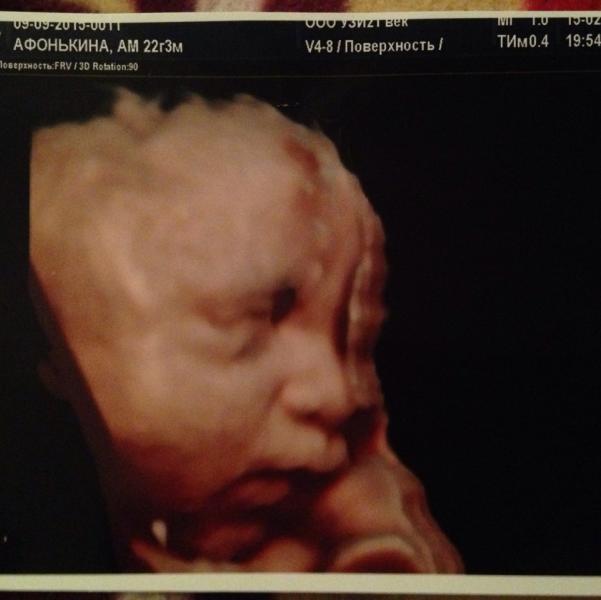

Сходили на узи 15.02.16 29 нед) просто так посмотреть как там наш сынуля) а он все отворачивался и закрывал личико ручками) ну ничего мы все равно его поймали и сделали наше первое фото)) малыш копия папули)))весит примерно 2кг не много ли на 29 нед то?! А так у нас все хорошо, я довольна)))

Какой красивый малышастик у вас 😍 даже не верится что в пузике такое чудо)

Моя дочь в 34 недели весила 2500, думаю крупноват малыш

Нам тоже 29 недель, а весим мы 1400🤔, врач сказала, что вес хороший.

Огого)) у нас в почти 27недель был 1кило, вот это богатырь у вас 💪🏼

крепыш:))))